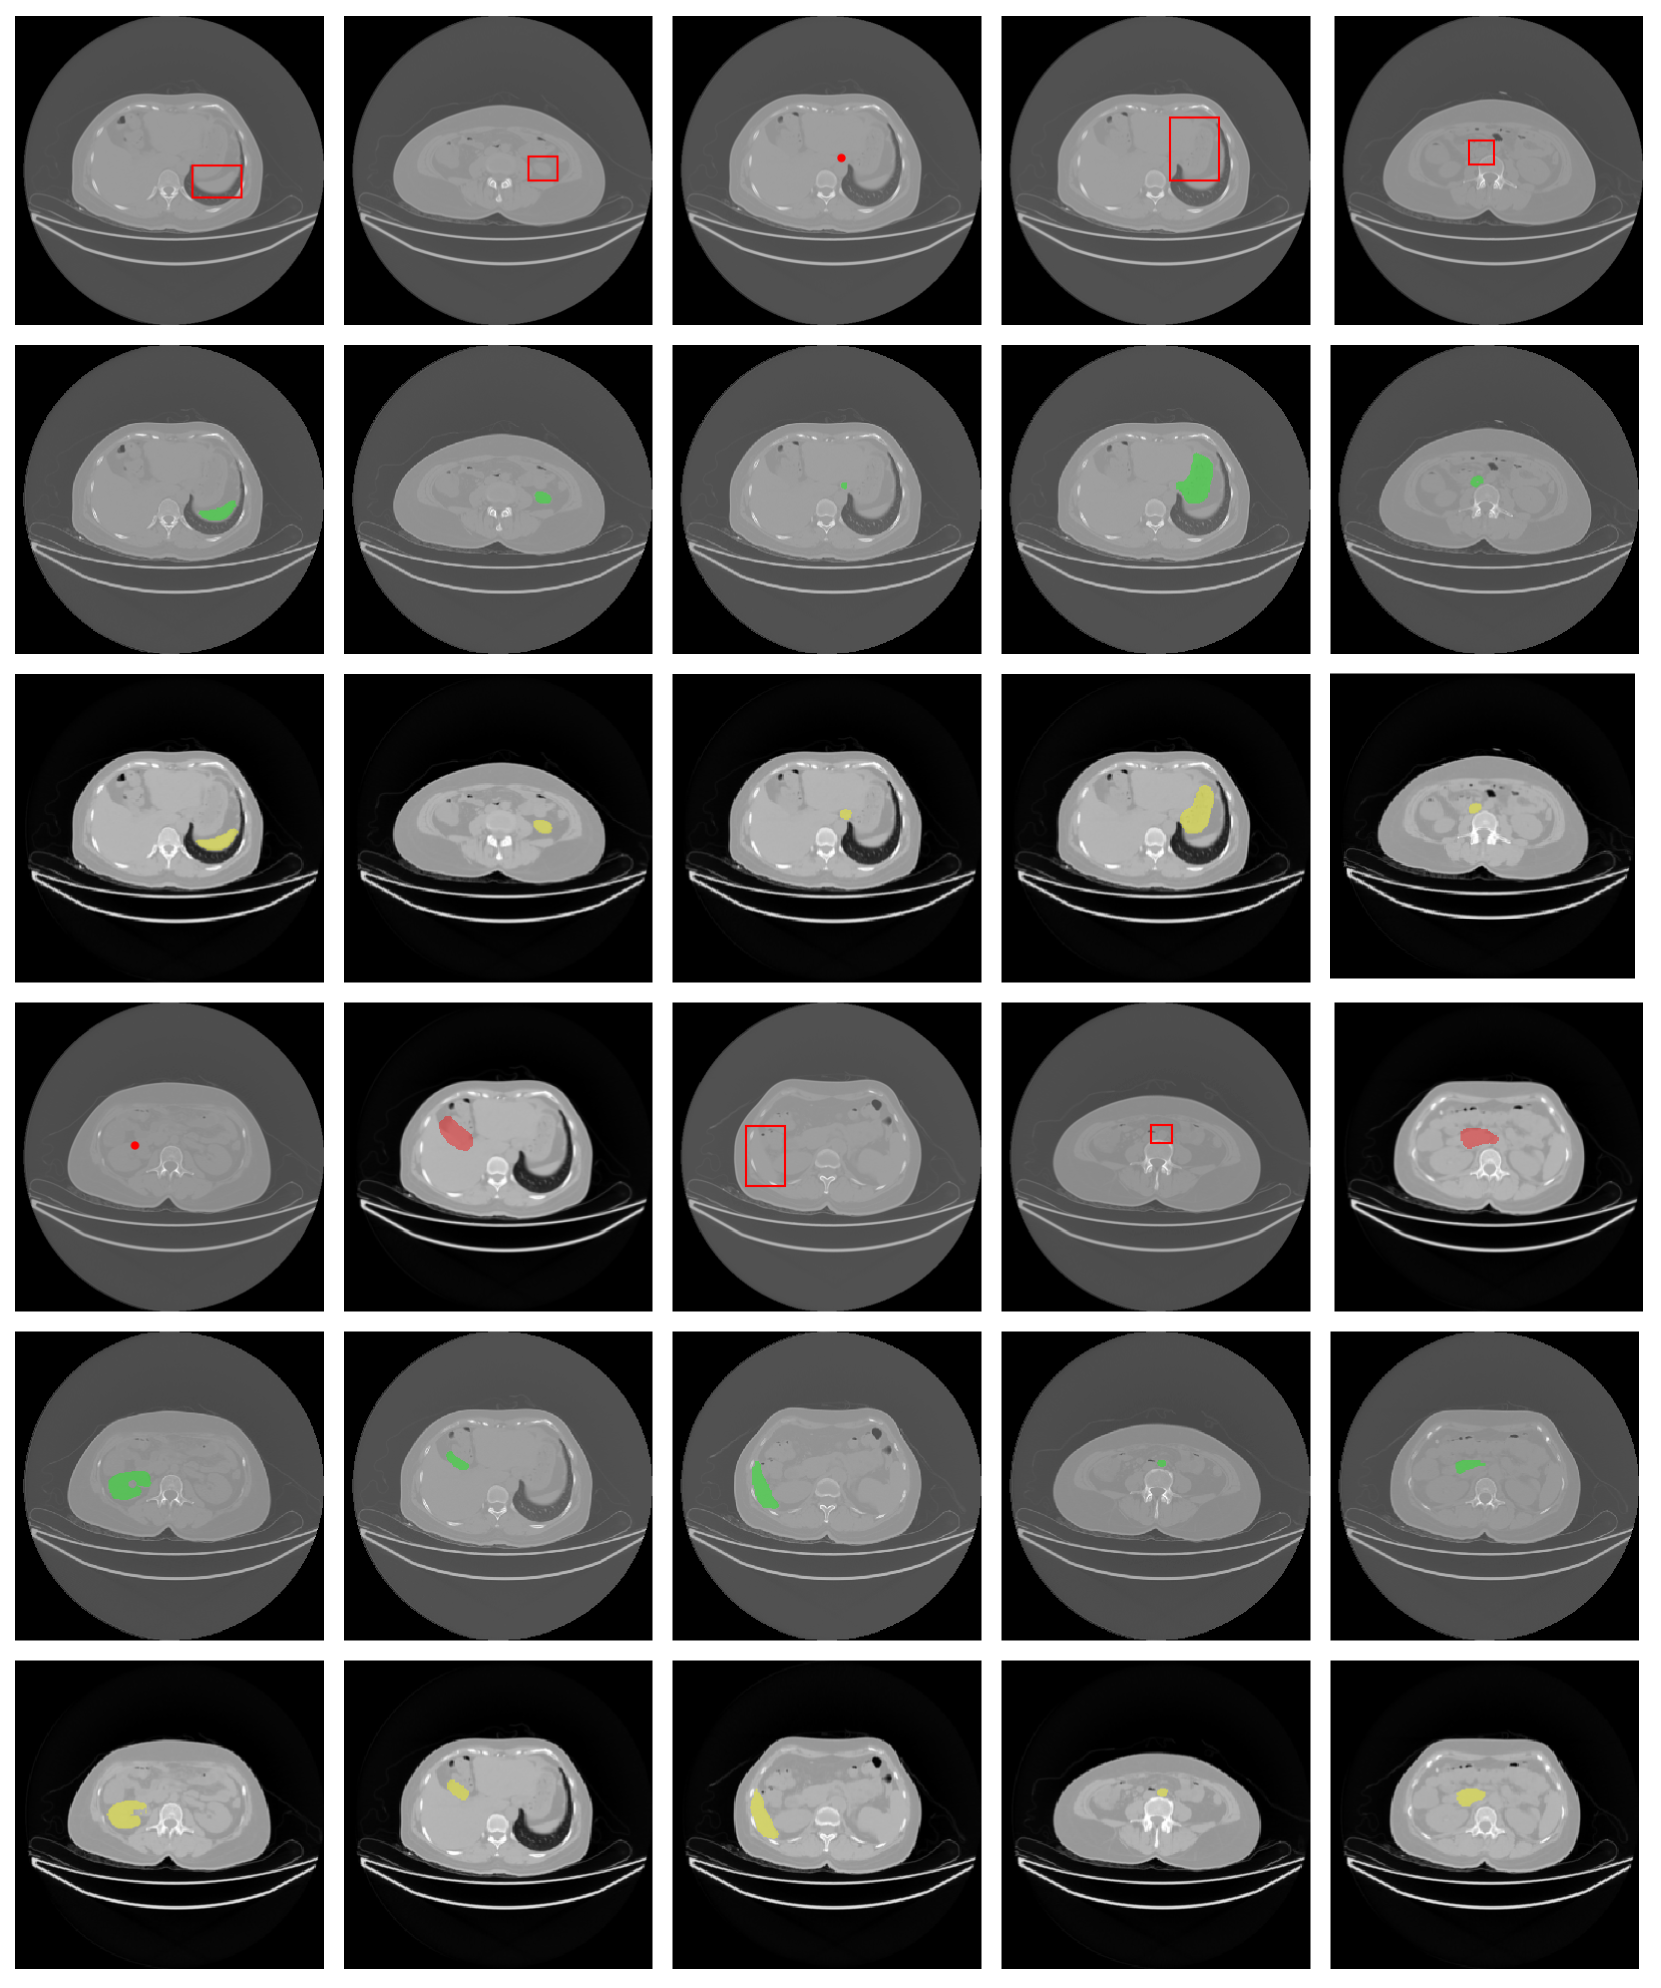

Figure 7 shows a qualitative example of our model’s predictions for each type of prompt: point, box, and mask. We display the prompt, the ground-truth mask, and the model’s prediction. We show additional qualitative examples in the supplementary materials.

Refer to caption

Figure 7: Qualitative results from various prompts. The prompt example appears in red, and on top, the ground truth mask appears in green under. At the bottom in yellow is the mask predicted by the model.

We show more qualitative results in Figure 10 using point, bbox, and mask as prompts.

Figure 10: Qualitative results of the model. The prompt example appears in red, the ground truth mask appears in green. At the bottom in yellow is the mask predicted by the model.